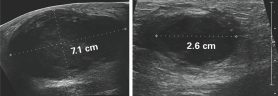

ARTEMIS está abierto a pacientes con TNBC de etapas I a III sin tratamiento previo que tengan tumores primarios de al menos 1.5 cm de diámetro. Se somete a todos los pacientes inscritos en ARTEMIS a una biopsia del tumor primario y a pruebas moleculares antes del tratamiento. Para determinar si las pruebas moleculares mejoran los resultados, se asigna a los pacientes de forma aleatoria a uno de dos grupos del estudio; cada paciente tiene 2 probabilidades sobre 3 de ser asignado al grupo B, que es el experimental. Los pacientes del grupo A no reciben los resultados de las pruebas moleculares; los del grupo B sí reciben los resultados.